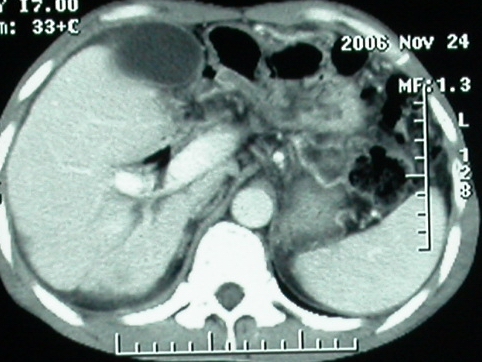

标题: CT5432:上腹隐痛、饱胀、消瘦2-月(尾状叶肝癌)。 [打印本页]

标题: CT5432:上腹隐痛、饱胀、消瘦2-月(尾状叶肝癌)。

男,57岁。

平扫

增强ct所见【动脉增强期】